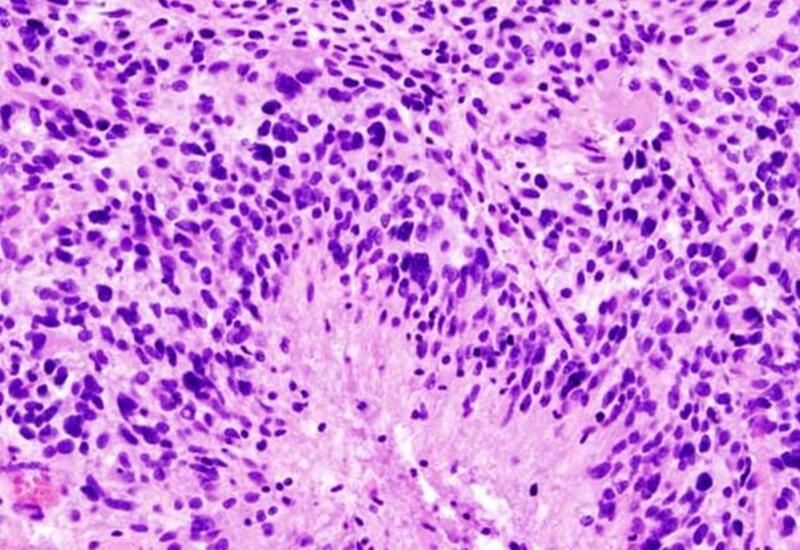

Ученые из Медицинского колледжа Альберта Эйнштейна показали, что глиобластома - самый агрессивный вид рака мозга - поражает не только мозг, но и кости черепа. Исследование, опубликованное в Nature Neuroscience (NN), выявило: опухоль разрушает черепные швы, изменяет состав костного мозга и нарушает работу иммунной системы, передает Day.Az со ссылкой на Lenta.ru.

Эксперименты на мышах и анализ снимков пациентов показали, что глиобластома вызывает истончение костей и расширение каналов между черепом и мозгом. По этим каналам к опухоли устремляются воспалительные клетки из костного мозга, делая ее более агрессивной и устойчивой к лечению.

Ученые зафиксировали серьезный дисбаланс иммунных клеток: увеличивается число воспалительных нейтрофилов, а защитные B-клетки почти исчезают. Это может объяснять, почему традиционные методы терапии, ориентированные только на мозг, оказываются малоэффективны.